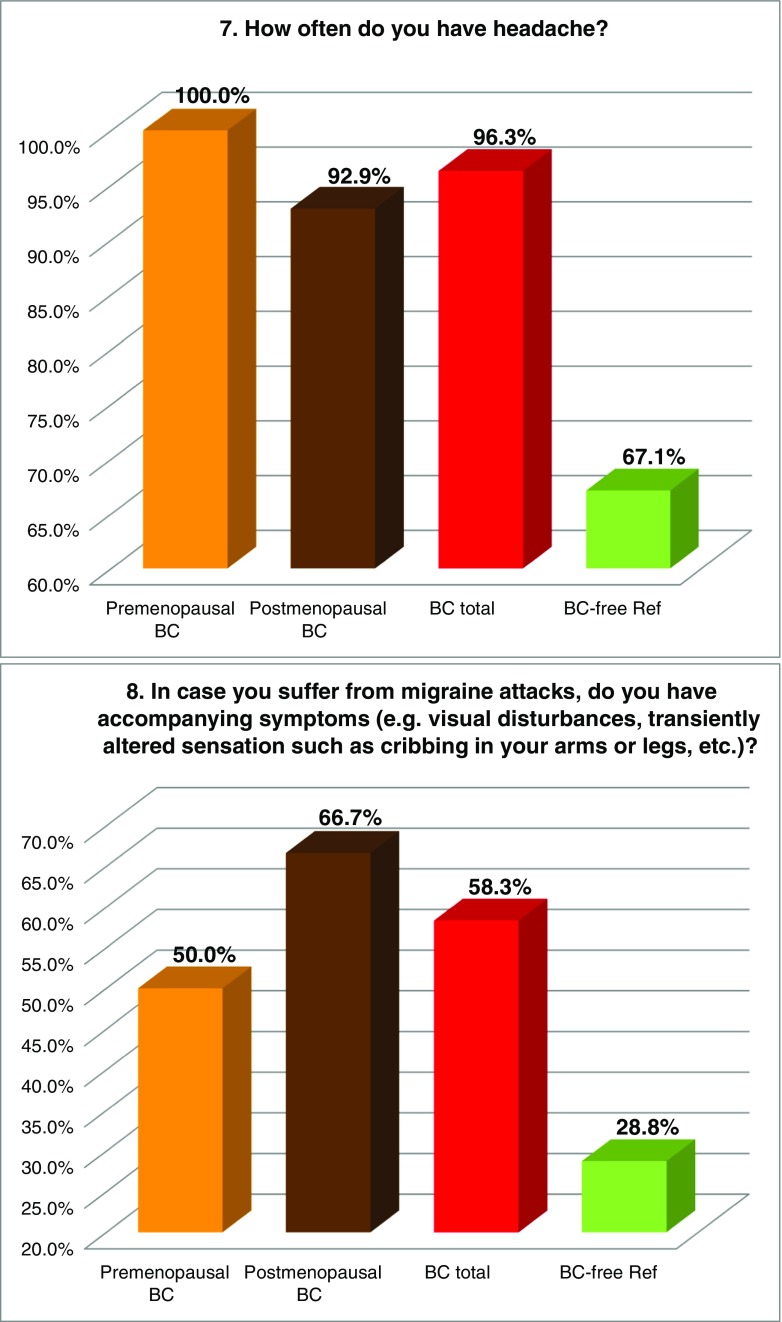

FS prevalence evaluated by individual symptoms

Figure 2 summarises the prevalence of individual “Flammer Syndrome” symptoms (1–15) in two main groups of comparison—“BC total” patients versus the reference group of “BC-free” individuals as well as in individual subgroups of BC patients subdivided according to their menopausal status. Higher prevalence in “BC total” (marked in red) has been demonstrated for all 15 symptoms investigated in this study. Statistical significance has been recorded for symptoms 1 (cold extremities), 2 (feeling cold), 5 (prolonged sleep onset), 7 (headache), 8 (accompanying symptoms), 9 (drug sensitivity) and 11 (smell perception); corresponding p values are provided in Table 3. Although being statistically non-significant (p = 0.103), a substantially greater prevalence has been demonstrated for symptom 6: “no feeling of thirst and drinking too little” the BC patients, in general, have demonstrated two times more frequently compared to the disease-free reference group; for the postmenopausal BC, this difference was even more pronounced. Also, the appearance of tinnitus (symptom 14), although being statistically non-significant (p = 0.095), was evidently more frequent in BC, particularly in the premenopausal subgroup demonstrating about two times higher prevalence compared to the disease-free reference group. Symptom 3 (low blood pressure) was more specific for the premenopausal BC demonstrating 22% higher prevalence against the disease-free reference group. In contrast, symptom 12 (low body weight in early adulthood) was more specific for postmenopausal BC. A slightly higher prevalence was demonstrated for symptom 4 (dizziness) in BC. Strong plurality has been demonstrated amongst the BC subgroups for the following three symptoms: 10 (pain, more specific for the postmenopausal BC), 13 (perfectionism, more specific for the postmenopausal BC) and 15 (skin blotches in stress, more specific for the premenopausal BC) as summarised in Table 3.

Fig. 2.

Evaluation of the prevalence of individual symptoms (1–15) of the “Flammer Syndrome” phenotype in two groups of comparison: “Breast cancer diseased” (BC total) versus “Breast cancer-free” reference (BC-free Ref) groups. Therein, the entire breast cancer patient pool (“BC total”) has been additionally analysed in subgroups stratified according to the menopausal status of the patients. For more details regarding the patient’s recruitment and stratification, see “Materials and methods” section. The prevalence in each individual group is presented by percentage of individuals who have responded to the corresponding question with “frequently” and “sometimes” pooled together. Responders answering with “I do not know” have been excluded from the overall numbers/calculations. Question-specific notes: question 6—the ratio between “I do not feel thirsty and drink little” and “I feel much thirsty and drink a lot” has been calculated and expressed as X times; question 12—answers “very slim” and “slim” are pooled together and presented in percentage

Table 3.

Symptoms of the “Flammer Syndrome” recorded in “Metastatic breast cancer patients” versus “Breast cancer-free individuals” groups of comparison

The table summarises the results demonstrated in Fig. 2; the following system is employed: “+” means higher prevalence of the corresponding symptom (above the lowest average of the groups of comparison); “−“ means lower prevalence of the corresponding symptom (lowest average and below it); “++“ means values sufficiently over the highest average. All 15 symptoms demonstrate increased prevalence in BC total versus BC-free. The level of significance is noted: p values below 0.05 are considered statistically significant and marked in red colour (symptoms 1, 2, 5, 7, 8, 9, 11). Thirteen symptoms united within the green-marked cluster demonstrate the prevalence ultimately increased in BC total as well as BC subgroups. Although the prevalence of symptoms 13 and 15 (yellow-marked cluster) is slightly increased in “BC total” compared to “BC-free,” it varies in BC subgroups demonstrating a particularly strong plurality amongst the patients with the metastatic BC investigated in the current study

The meaning of individual FS symptoms specifically for the BC patient cohort has been discussed in detail in the recently published article “Breast Cancer and Flammer Syndrome: Any Symptoms in Common for Prediction, Prevention and Personalised Medical Approach?” [28]. Current chapter emphasises a particular relevance of the FS symptoms for the metastatic disease in the BC patient cohort: all 15 symptoms demonstrate the prevalence in the metastatic BC versus BC-free reference group with a statistical significance (p ≤ 0.05) for seven symptoms as summarised in Table 3. Other symptoms, even being statistically non-significantly prevalent within this study, can be of great importance for the BC pathology and metastatic disease. Hence, symptom 3 (low blood pressure, p = 0.127) is particularly relevant for the premenopausal subgroup and may strongly contribute the cardio-vascular component characteristic for the FS as explained above. Another example is the following: symptom 4 (dizziness, p = 0.762) has been described earlier as being permanently present and stepwise worsening in BC followed by metastasis in the brain [20, 33]. Finally, the normal feeling of thirst (symptom 6, p = 0.103) is extremely important and if diminished (here two times in BC versus BC-free) plays a crucial role in the body dehydration and BC development [20].